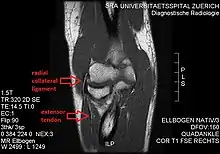

The radial collateral ligament (RCL), lateral collateral ligament (LCL), or external lateral ligament[Explain 1] is a ligament in the elbow on the side of the radius.

- the radial collateral ligament [proper] (RCL), from the lateral epicondyle to the annular ligament deep to the common extensor tendon[1]

- the lateral ulnar collateral ligament (LUCL), from the lateral epicondyle[3] to the supinator crest on the ulna. Near the attachment on the humerus this ligament is normally indistinguishable from the RCL and can be considered the posterior portion of it.[1] Martin 1958 described the distal part of the LUCL as "a definite bundle which normally crosses the annular band and gains attachment to the supinator crest, frequently to a special tubercle on that crest" but didn't name it.[4]